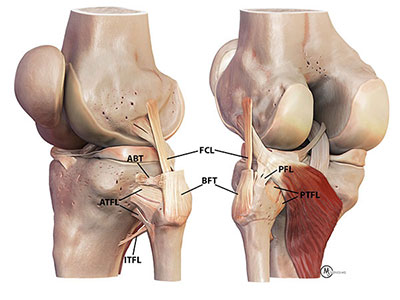

- The proximal tibiofibular joint (PTFJ) is the articulation of the lateral tibial plateau of the tibia and the head of the fibula. The fibular head lies in an angled groove behind the lateral tibial ridge, which helps to prevent anterior fibular movement with knee flexion [7]. The proximal fibula moves posteromedial with knee extension. The anterolateral and posteromedial sliding movement of this joint reduces torsional forces from the ankle, prevents lateral bending of the tibia, spreads the axial load while standing, and helps to stabilize the knee [2]. The PTFJ capsule is stabilized by anterior and posterior tibiofibular ligaments, lateral collateral ligament, popliteus, and biceps femoris tendon (BFT). The lateral collateral ligament compresses the fibular head to the tibia and is tight from 0° to 30° of knee flexion. A layer of the biceps femoris tendon wraps anteriorly to the anterior PTFL to insert onto Gerdy's tubercle, which is where the IT band attaches on the tibia. This reinforces the joint with anterolateral movement of the fibular head.